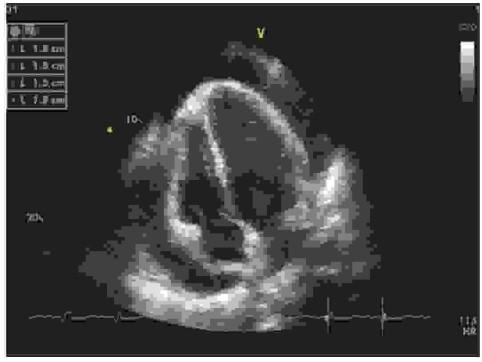

W trzeciej dobie po CABG chory ma gorszą tolerancję wysiłku. W badaniu fizykalnym uwagę zwróciły wyraźniej wypełnione żyły szyjne oraz chłodne, pozbawione tętna stopy. Osłuchowo stwierdzono ściszone tony serca, a w EKG stwierdzono tachykardię zatokową, małą amplitudę zespołów QRS oraz załamków T, a także naprzemienność elektryczną zespołów QRS. Na podstawie powyższych danych oraz obrazu echokardiograficznego wskaż prawidłowe postępowanie: